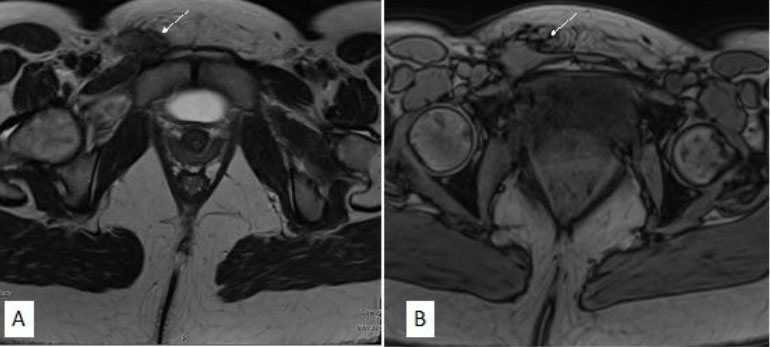

A 31-year-old nulligravid woman with medical history notable for cerebral palsy and without history of intra-abdominal surgery presented for an annual well-woman visit with a painful, right inguinal mass. On initial evaluation, the <1 cm mildly tender lesion was suspected to be an ingrown hair. Over the course of one year, the patient represented, reporting that the mass had become “deeper, firmer, and larger.” Physical examination at the time was notable for a 3-cm non-mobile firm mass in her right inguinal fold. The patient reported that the pain was intermittent, occurring multiple times throughout the day, and not related to her menses. She had no symptoms of intra-pelvic endometriosis, including history of dysmenorrhea, chronic pelvic pain, abdominal pain, dyspareunia, dyschezia, or dysuria. The patient had never used hormonal suppression throughout her reproductive lifetime. A computed tomography (CT) of the abdomen and pelvis was initially obtained for consideration of an inguinal hernia and was notable for an irregular 2–3 cm soft tissue nodule in the right inguinal region (Figure 1). Subsequent magnetic resonance imaging (MRI) of the abdomen and pelvis was obtained to further characterize the nodule and revealed a right inguinal 2–3-cm ill-defined, soft tissue lesion adherent to the fascia. The lesion was hypointense on T2-weighted sequence and moderately intense lesion with a few foci of hyperintense signal on T1-weighted sequence, favoring endometriosis (Figure 2). The visceral pelvis was without evidence of endometriosis on imaging.

Figure 2: MRI of the abdomen and pelvis with a right-sided inguinal lesion concerning for endometriosis. A sagittal view of the pelvis with a right inguinal 2–3-cm ill-defined, soft tissue lesion adherent to the fascia. (A) On T2-weighted sequence the lesion is hypointense. (B) On T1-weighted sequence the lesion is intermediate with a few foci of hyperintense signal favoring endometriosis.